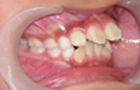

| 症状 | 前歯が飛び出していてお口が閉じにくい状態です。 身体が傾いてしまっています。 |

| 治療法 | 拡大装置にて上顎歯列の拡大を行い、機能矯正装置にて下顎位の是正、下顎の発育促進を行った |

横向き寝やうつぶせ、頬杖などに気をつけて治療をし、V字型だった歯並びが本来のU字型になってきました。

これで永久歯を抜かないで治療することができるようになりました。飛び出していた前歯がだんだん咬みあってきました。